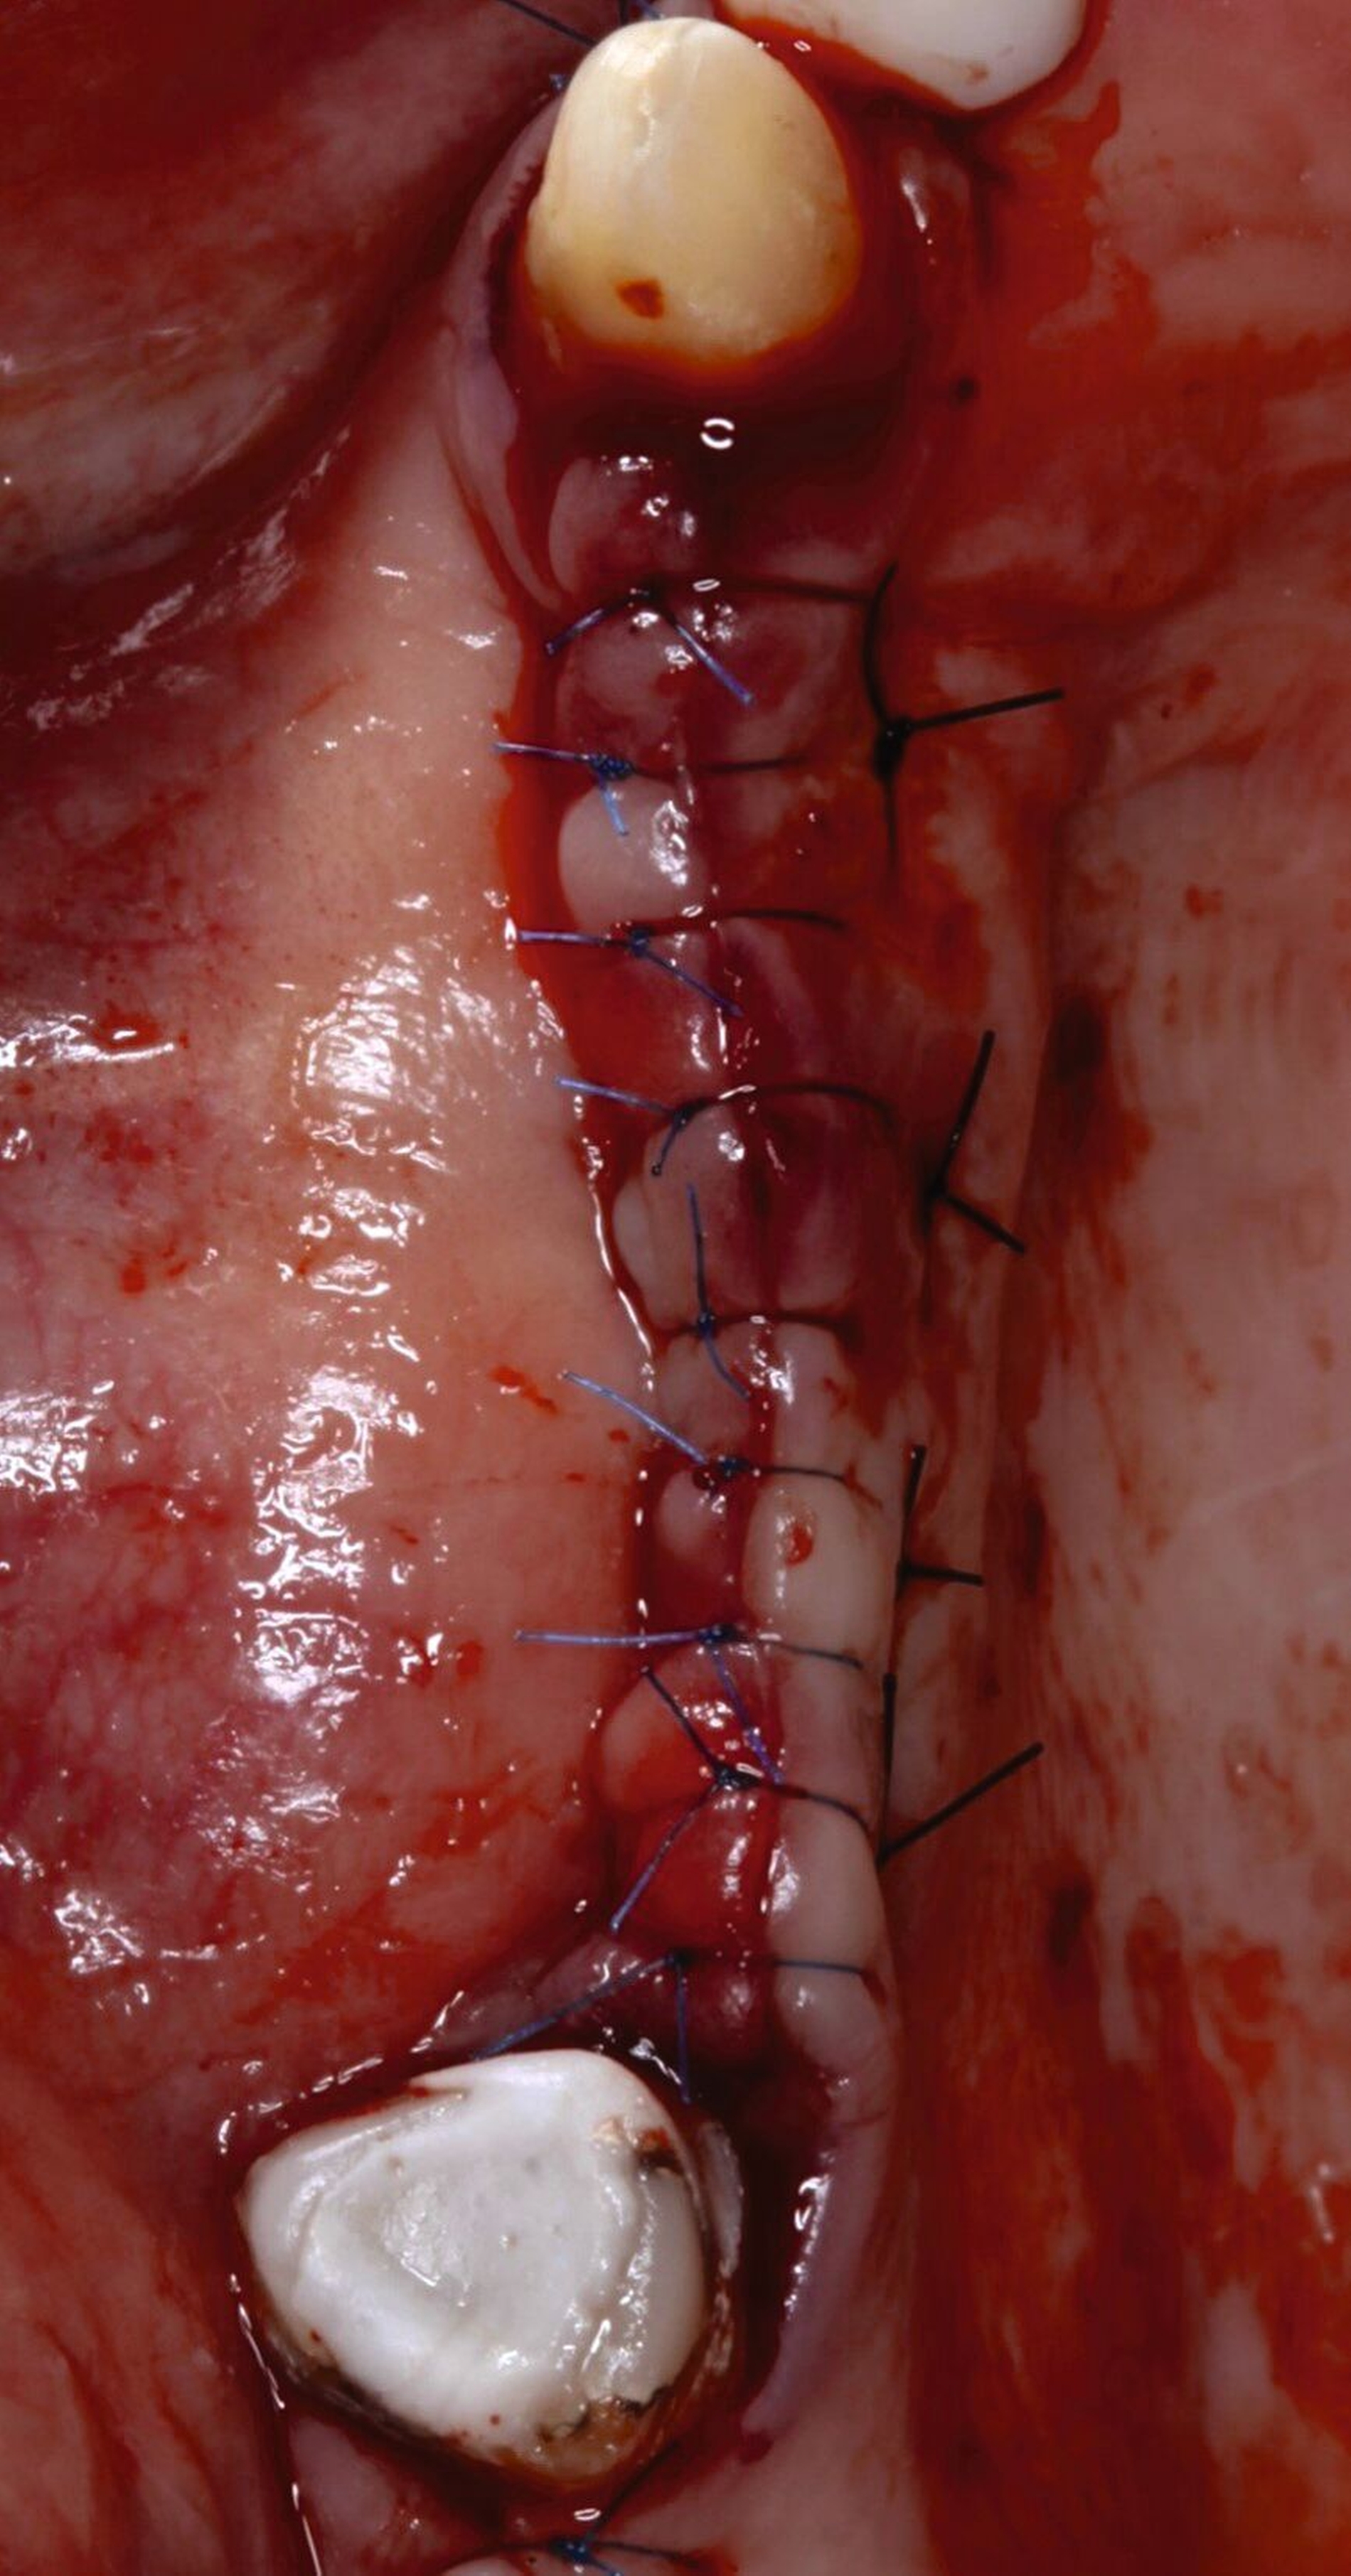

Fall 2 – complex (chirurgisch/prothetisch)

Der zweite Fall zeigt, dass nicht alle implantologischen Behandlungen chirurgisch als straightforward (S) eingestuft werden können. Während im Straightforward-Fall ein Behandler ausreichte, war im komplexen Fall die Expertise von zwei spezialisierten Kollegen nötig. Dies verdeutlicht, dass die Einschätzung der Komplexität vor Behandlungsbeginn entscheidend ist, um den optimalen Behandlungsweg zu wählen und das bestmögliche Ergebnis zu erzielen.

Fall 2: Chirurgie: Prof. Dr. Stimmelmayr, Prothetik: Univ.-Prof. Dr. Beuer, MME